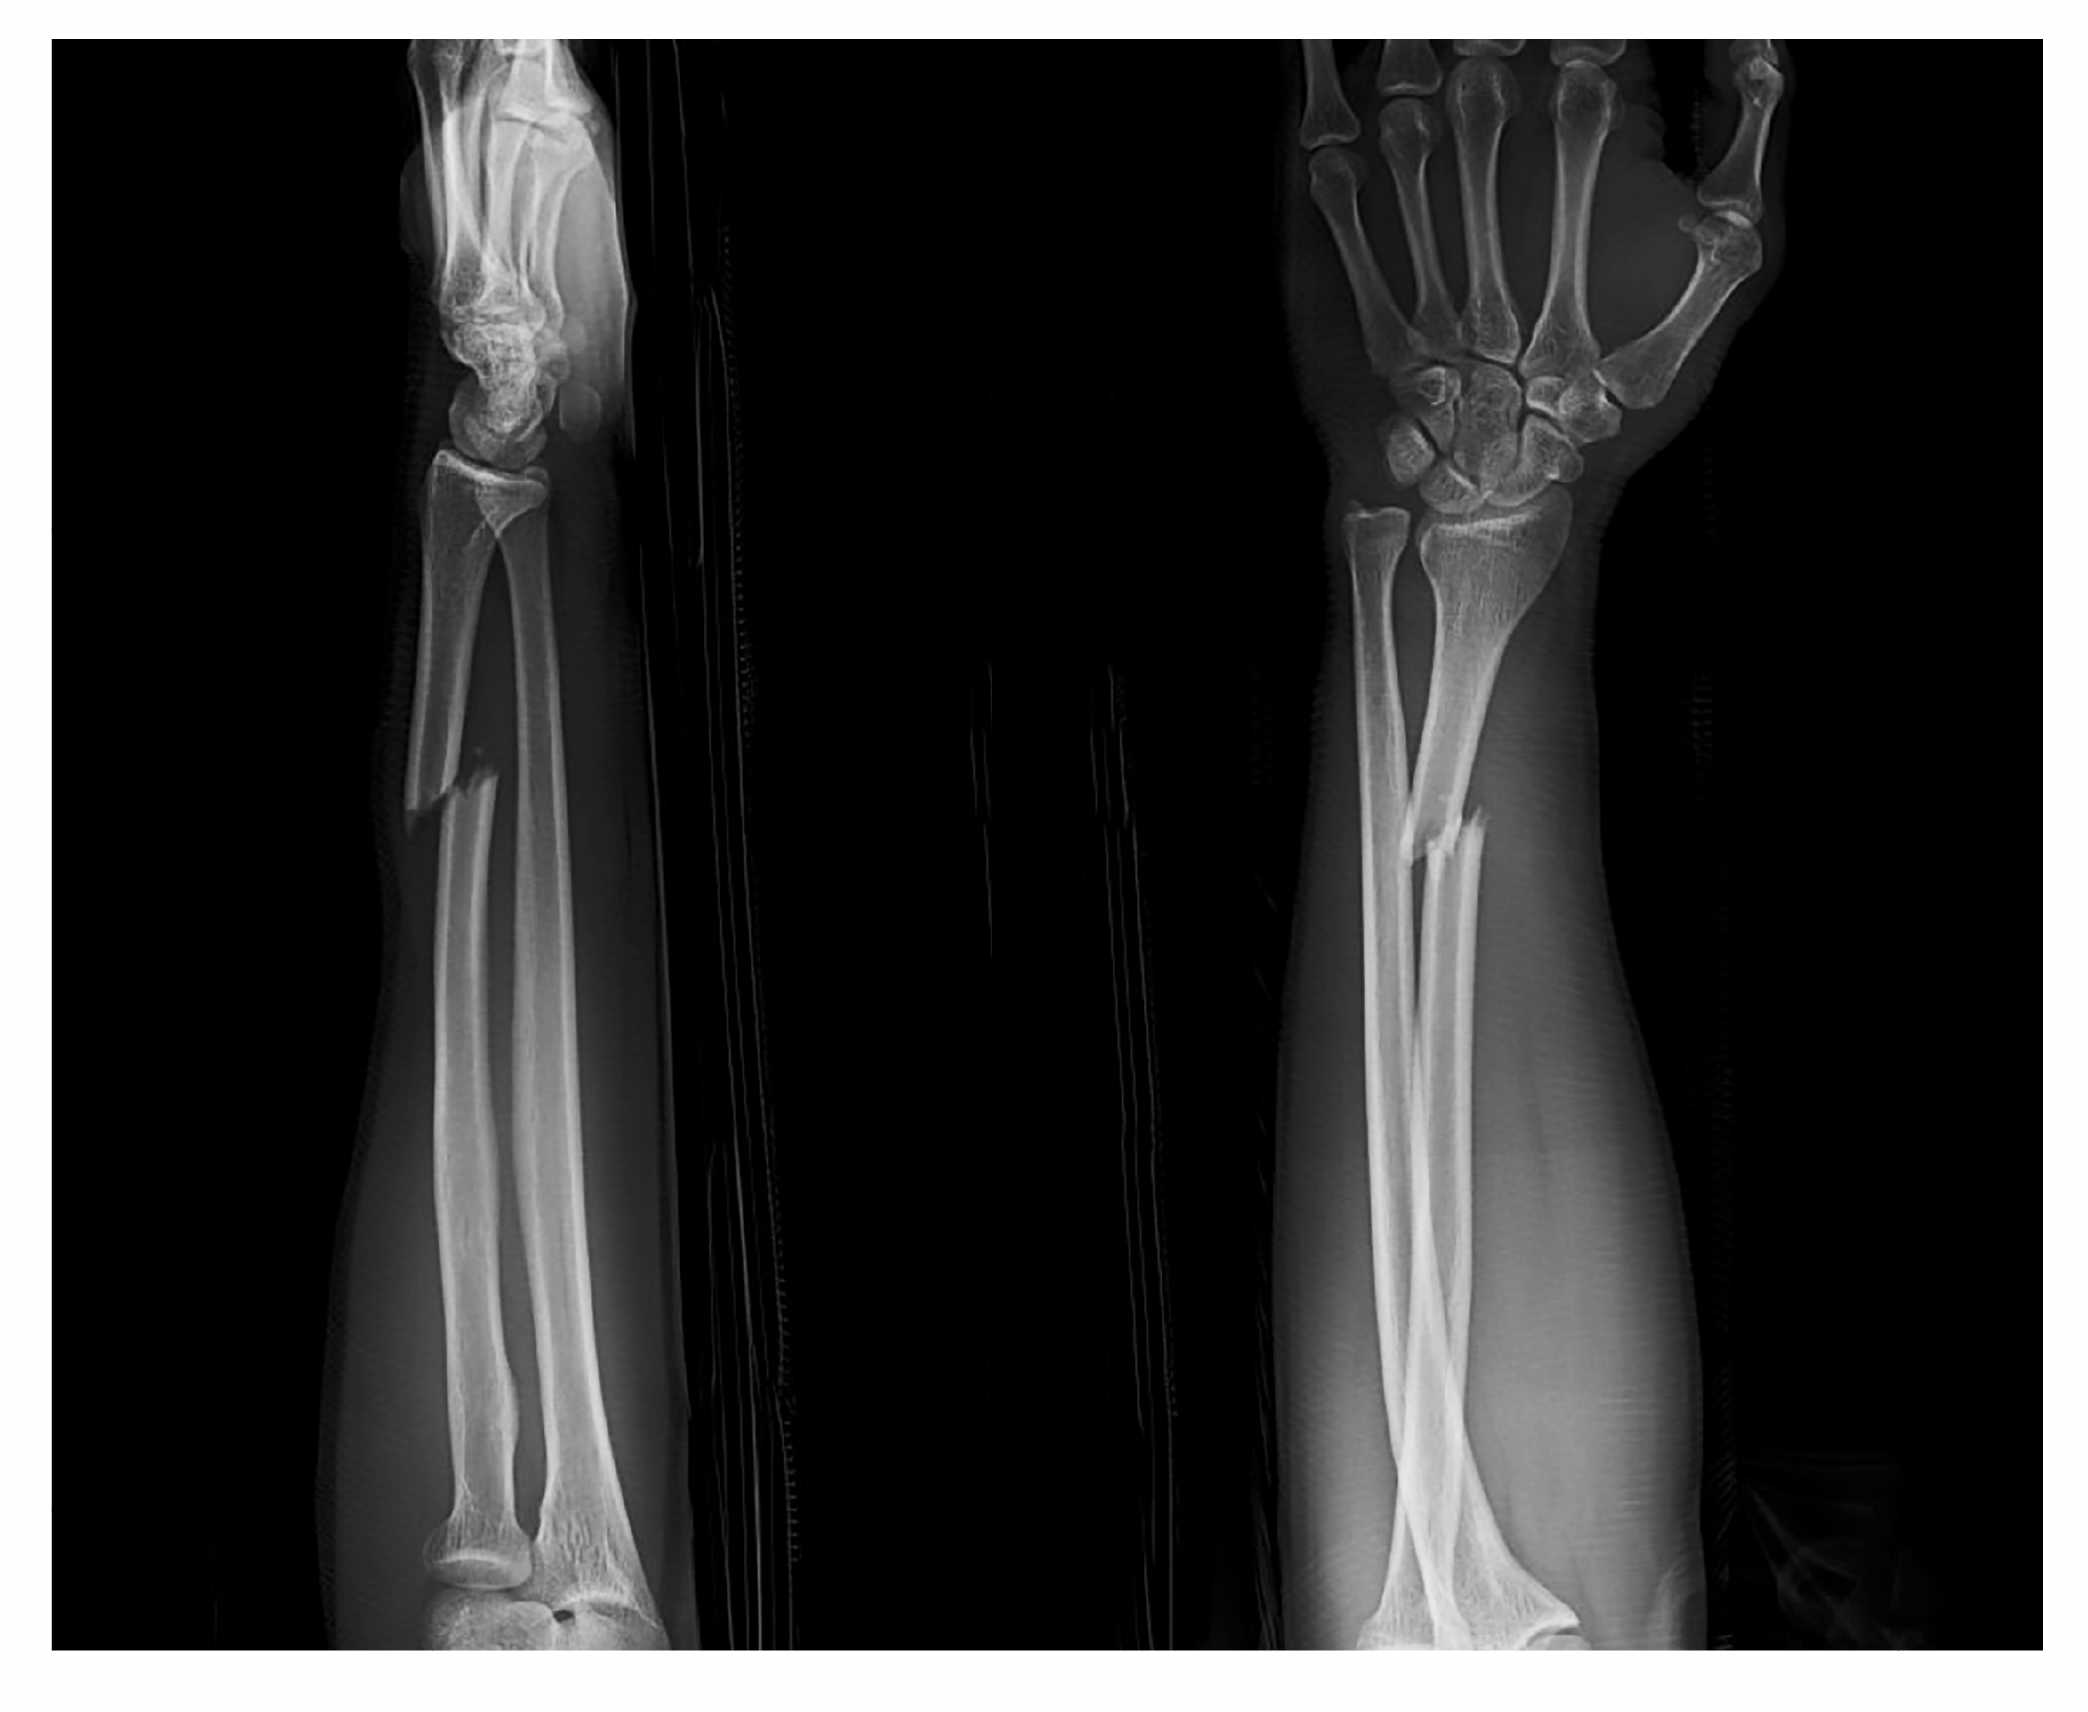

A 32-year-old man presents to the ED after a fall off of a skateboard. His X-ray is shown above. Which of the following physical exams will evaluate for the most commonly associated nerve injury in this type of fracture?

Median nerve injury (anterior interosseous nerve)